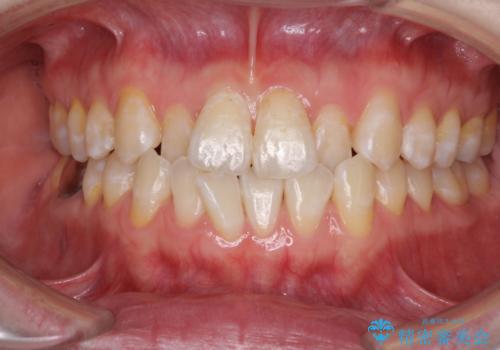

ワイヤーによる全体的ながたつきの矯正治療